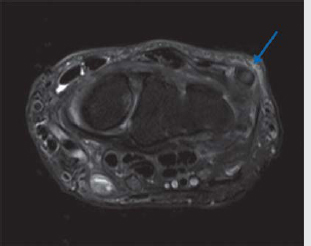

Extensor carpi ulnaris (ECU) tendinopathy

Common cause of ulnar sided pain.

Tendinosis is T2 hyperintense (grayish), unlike normal black tendon signal (► Fig. 4.3).

Partial tears will have T2 hyperintense (white) fluid clefts.

Can have associated tenosynovitis—T2 hyperintense fluid rim around ECU.